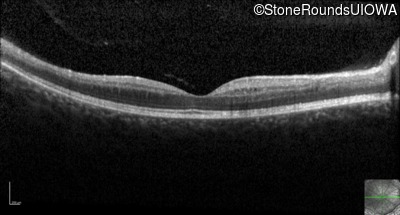

Visit at age: 18 years

Optical Coherence Tomography - Right - 20/40 +2

Exemplar / OCT Stack

OCT Stack